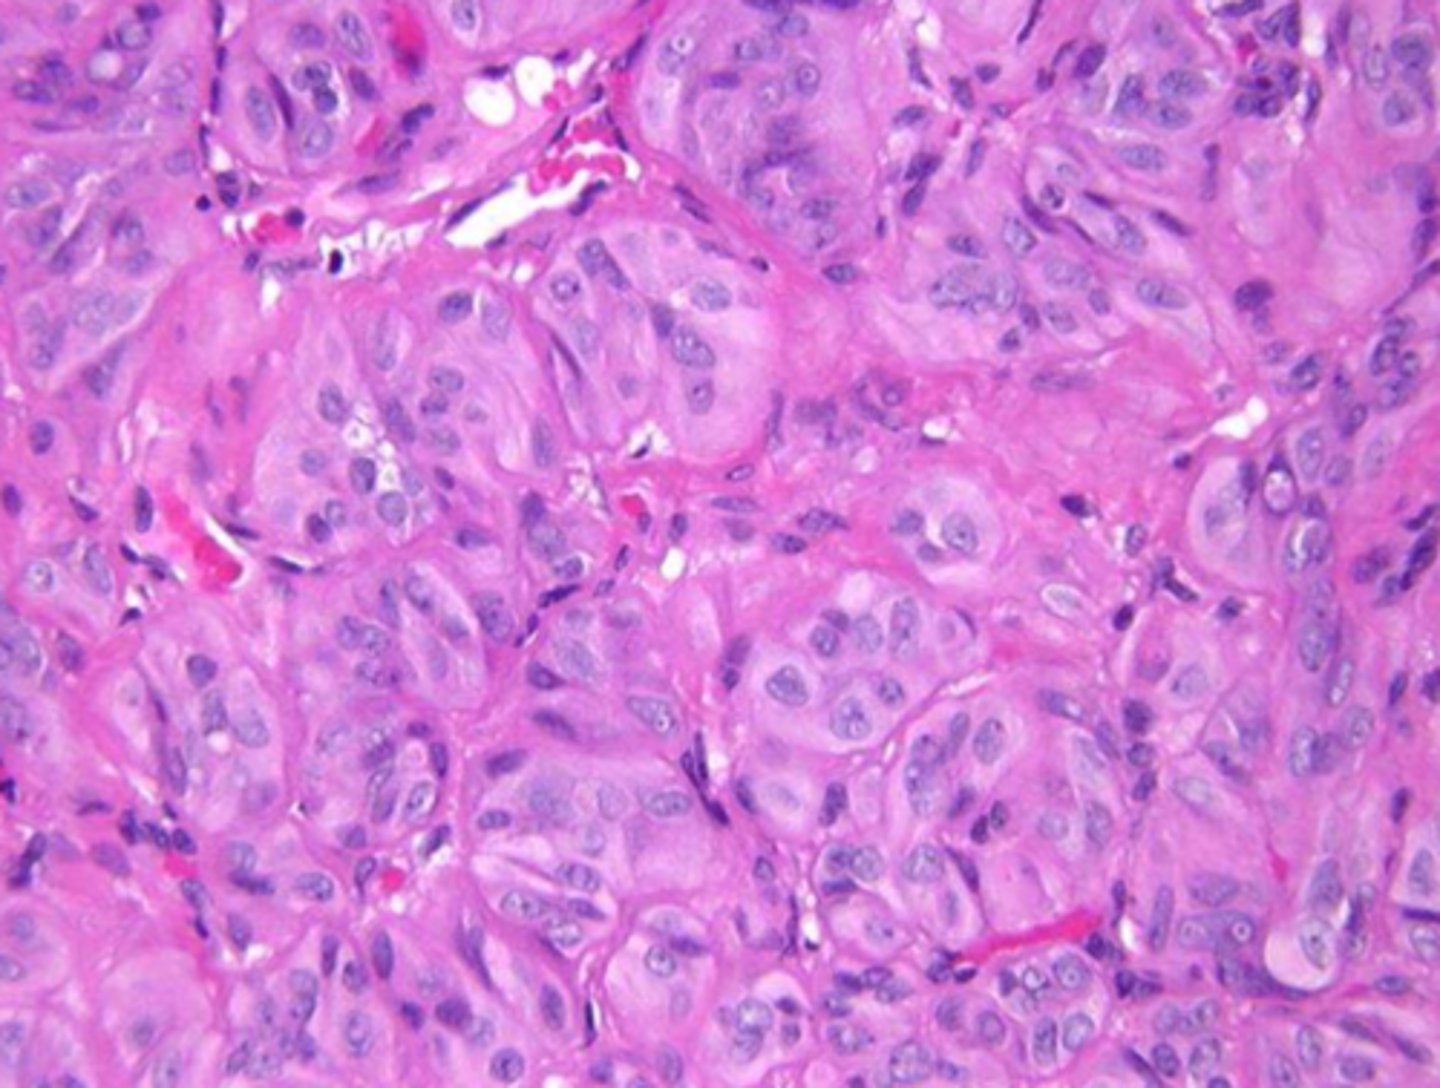

-clear/empty appearance---> ground glass or orphan annie eye nuclei

nuclear morphology of pappillary carcinoma

orphan annie eye nuclei

Seen in Papillary Carcinoma of the Thyroid. Enlarged thyroid cells with ground glass nuclei

<p>Seen in Papillary Carcinoma of the Thyroid. Enlarged thyroid cells with ground glass nuclei</p>